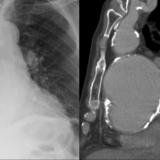

Aortic aneurysm withl ateral

Date: 03/02/2014

Views: 2338